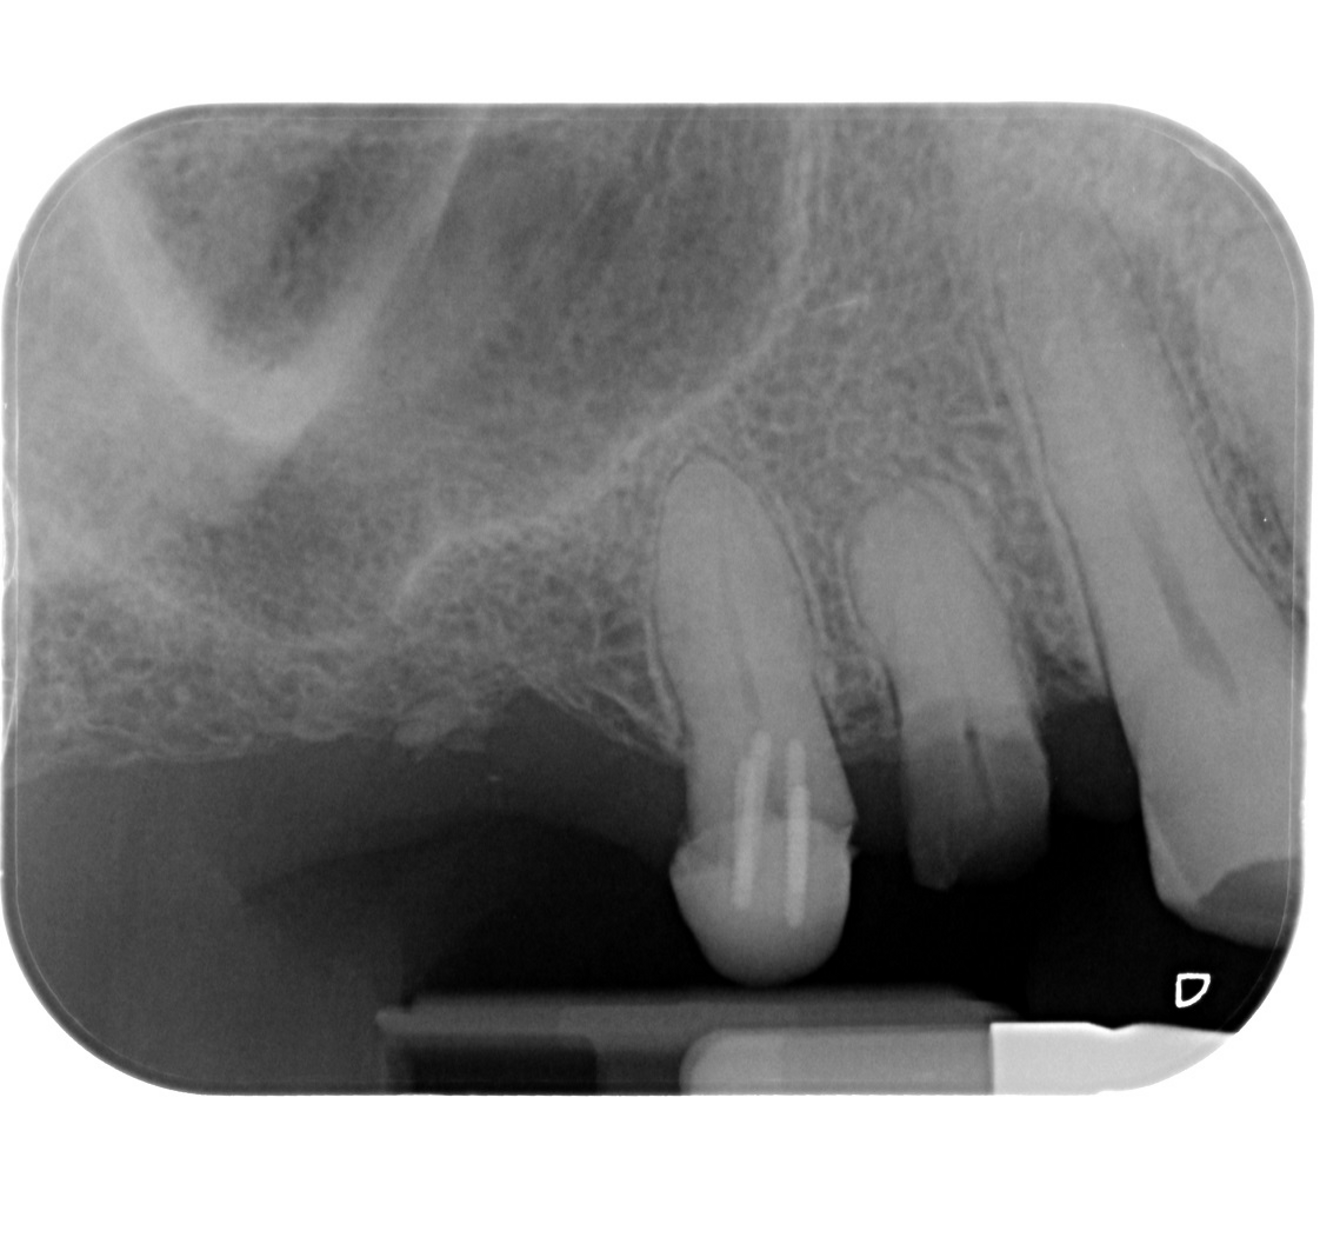

Fig. 3: Initial periapical radiograph.

A male patient presented in our dental office with a severely broken maxillary right first premolar (tooth #14) that had been designated for extraction a number of years before. The tooth immediately distal (tooth #15) was also in need of substantial dental treatment (Figs. 1 & 2). The patient had hypertension that was controlled with anti-hypertensive medication, but was otherwise medically fit. He intended to have the colour of his anterior teeth improved, but wished to address the issues on his maxillary right side first.

Tooth #14 was deemed unrestorable, and so it was decided to extract the tooth (Figs. 3 & 4), wait for bony healing and replace it with an implant with a provisional restoration. During the healing process, endodontic therapy would be performed on tooth #15. After bony integration, implant #14 would be restored with a screw-retained direct-to-implant zirconia crown, and tooth #15 would also be restored with a complete zirconia crown. A deliberately lighter shade would be chosen, factoring in the patient’s long-term desire to improve the colour of his teeth.